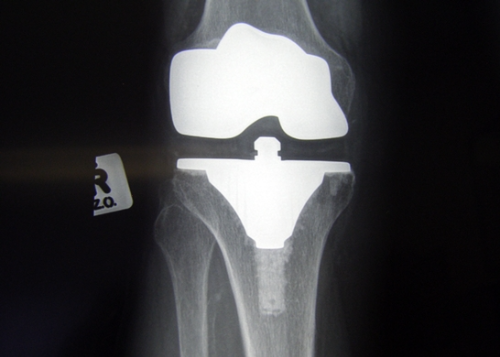

- 정형외과 치료: 연골 손상이 심할 경우 물리치료나 수술 고려